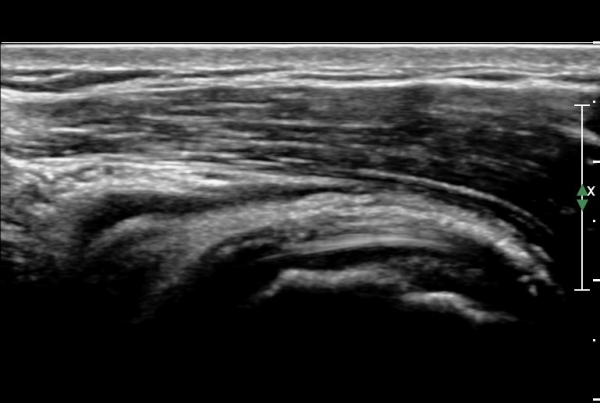

¿À±¸µ¹±â°ßºÀÀδë Á¾´Ü¸é°Ë»ç¿¡¼­ ÀÎ´ë ½ÉÃþ¿¡ ¼ö¾×Àú·ù°¡ °üÂûµÊ(»çÁø 1, 2)

ÀÌ´Â Ãæµ¹ÁõÈıºÀ» ¾Ï½ÃÇÏ´Â ¼Ò°ßÀÓ.